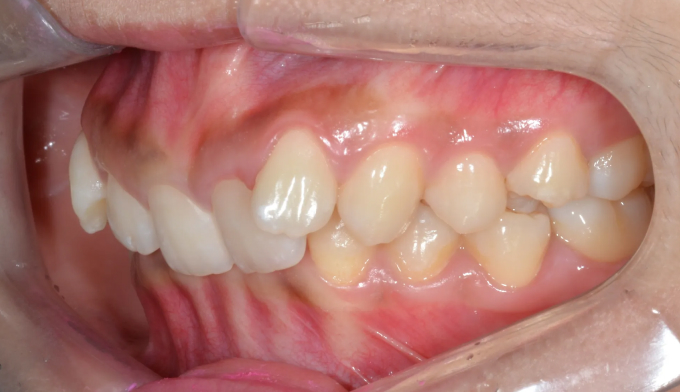

교정치료는 23개월 소요되었습니다.

아래 앞니가 선천적으로 하나 없는 경우여서 위아래 가운데선을 맞추지 않고 좌우대칭에 더 신경쓰기로 하였습니다. 위아래 치아 갯수에 차이가 나기 때문에 어쩔 수 없이 어금니 부근의 교합이 완벽하지 못하게 종료될것으로 보였지만 환자 스스로 불편감을 느끼지 못하기 때문에 심미적인면에 더 집중하기로 하고 종료하였습니다.

교합과 심미에 정답은 없습니다.

교합으로인해 불편감을 느끼지 않는다면 환자 스스로의 만족감이 교정치료의 최우선 목표입니다.